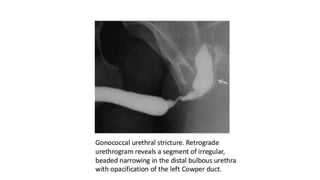

Role of urethrography in stricture

โ€ข Accurately delineates the anatomy of urethra.

โ€ข Location, number and extent of the strictures are very well displayed

โ€ข Delineation of the bladder neck and urethra is best achieved on the

MCU in the oblique projection.

โ€ข Secondary changes in the bladder.

โ€ข To demonstrate the VUR

โ€ข Visualization of any associated fistulas.